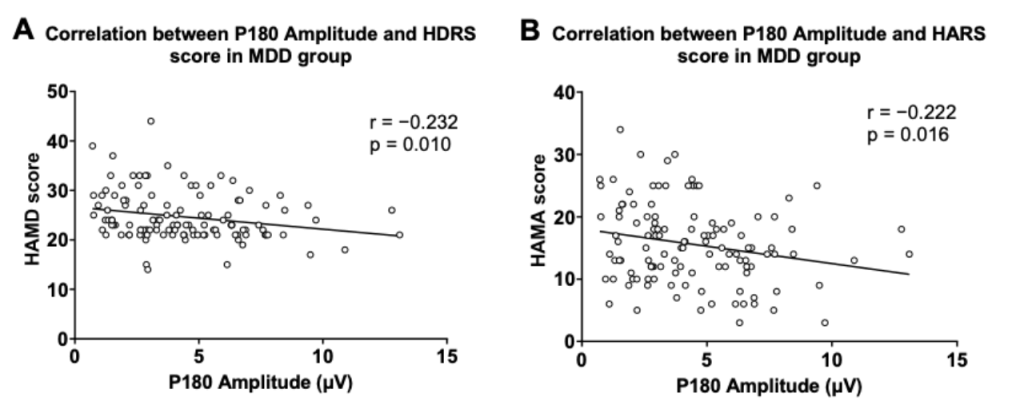

圖2. P180波幅與抑郁及焦慮癥狀得分的關(guān)系

圖1分別顯示了健康對(duì)照組與患者組的TMS誘發(fā)腦電的蝴蝶圖。研究結(jié)果顯示,抑郁癥患者P180波幅顯著低于健康對(duì)照人群。在抑郁癥患者中,P180波幅與抑郁、焦慮癥狀得分呈顯著負(fù)相關(guān);P30波幅與RBANS視覺(jué)空間/結(jié)構(gòu)得分和總分呈顯著負(fù)相關(guān)。

多元回歸分析表明,P180波幅能負(fù)向預(yù)測(cè)患者的抑郁及焦慮癥狀;P30波幅、發(fā)病年齡和教育程度能負(fù)向預(yù)測(cè)患者的認(rèn)知功能。

P180作為抑郁及焦慮癥狀的標(biāo)記物,P30作為認(rèn)知損傷的標(biāo)記物,可能反映了抑郁癥患者背外側(cè)前額葉皮質(zhì)的興奮-抑制不平衡。